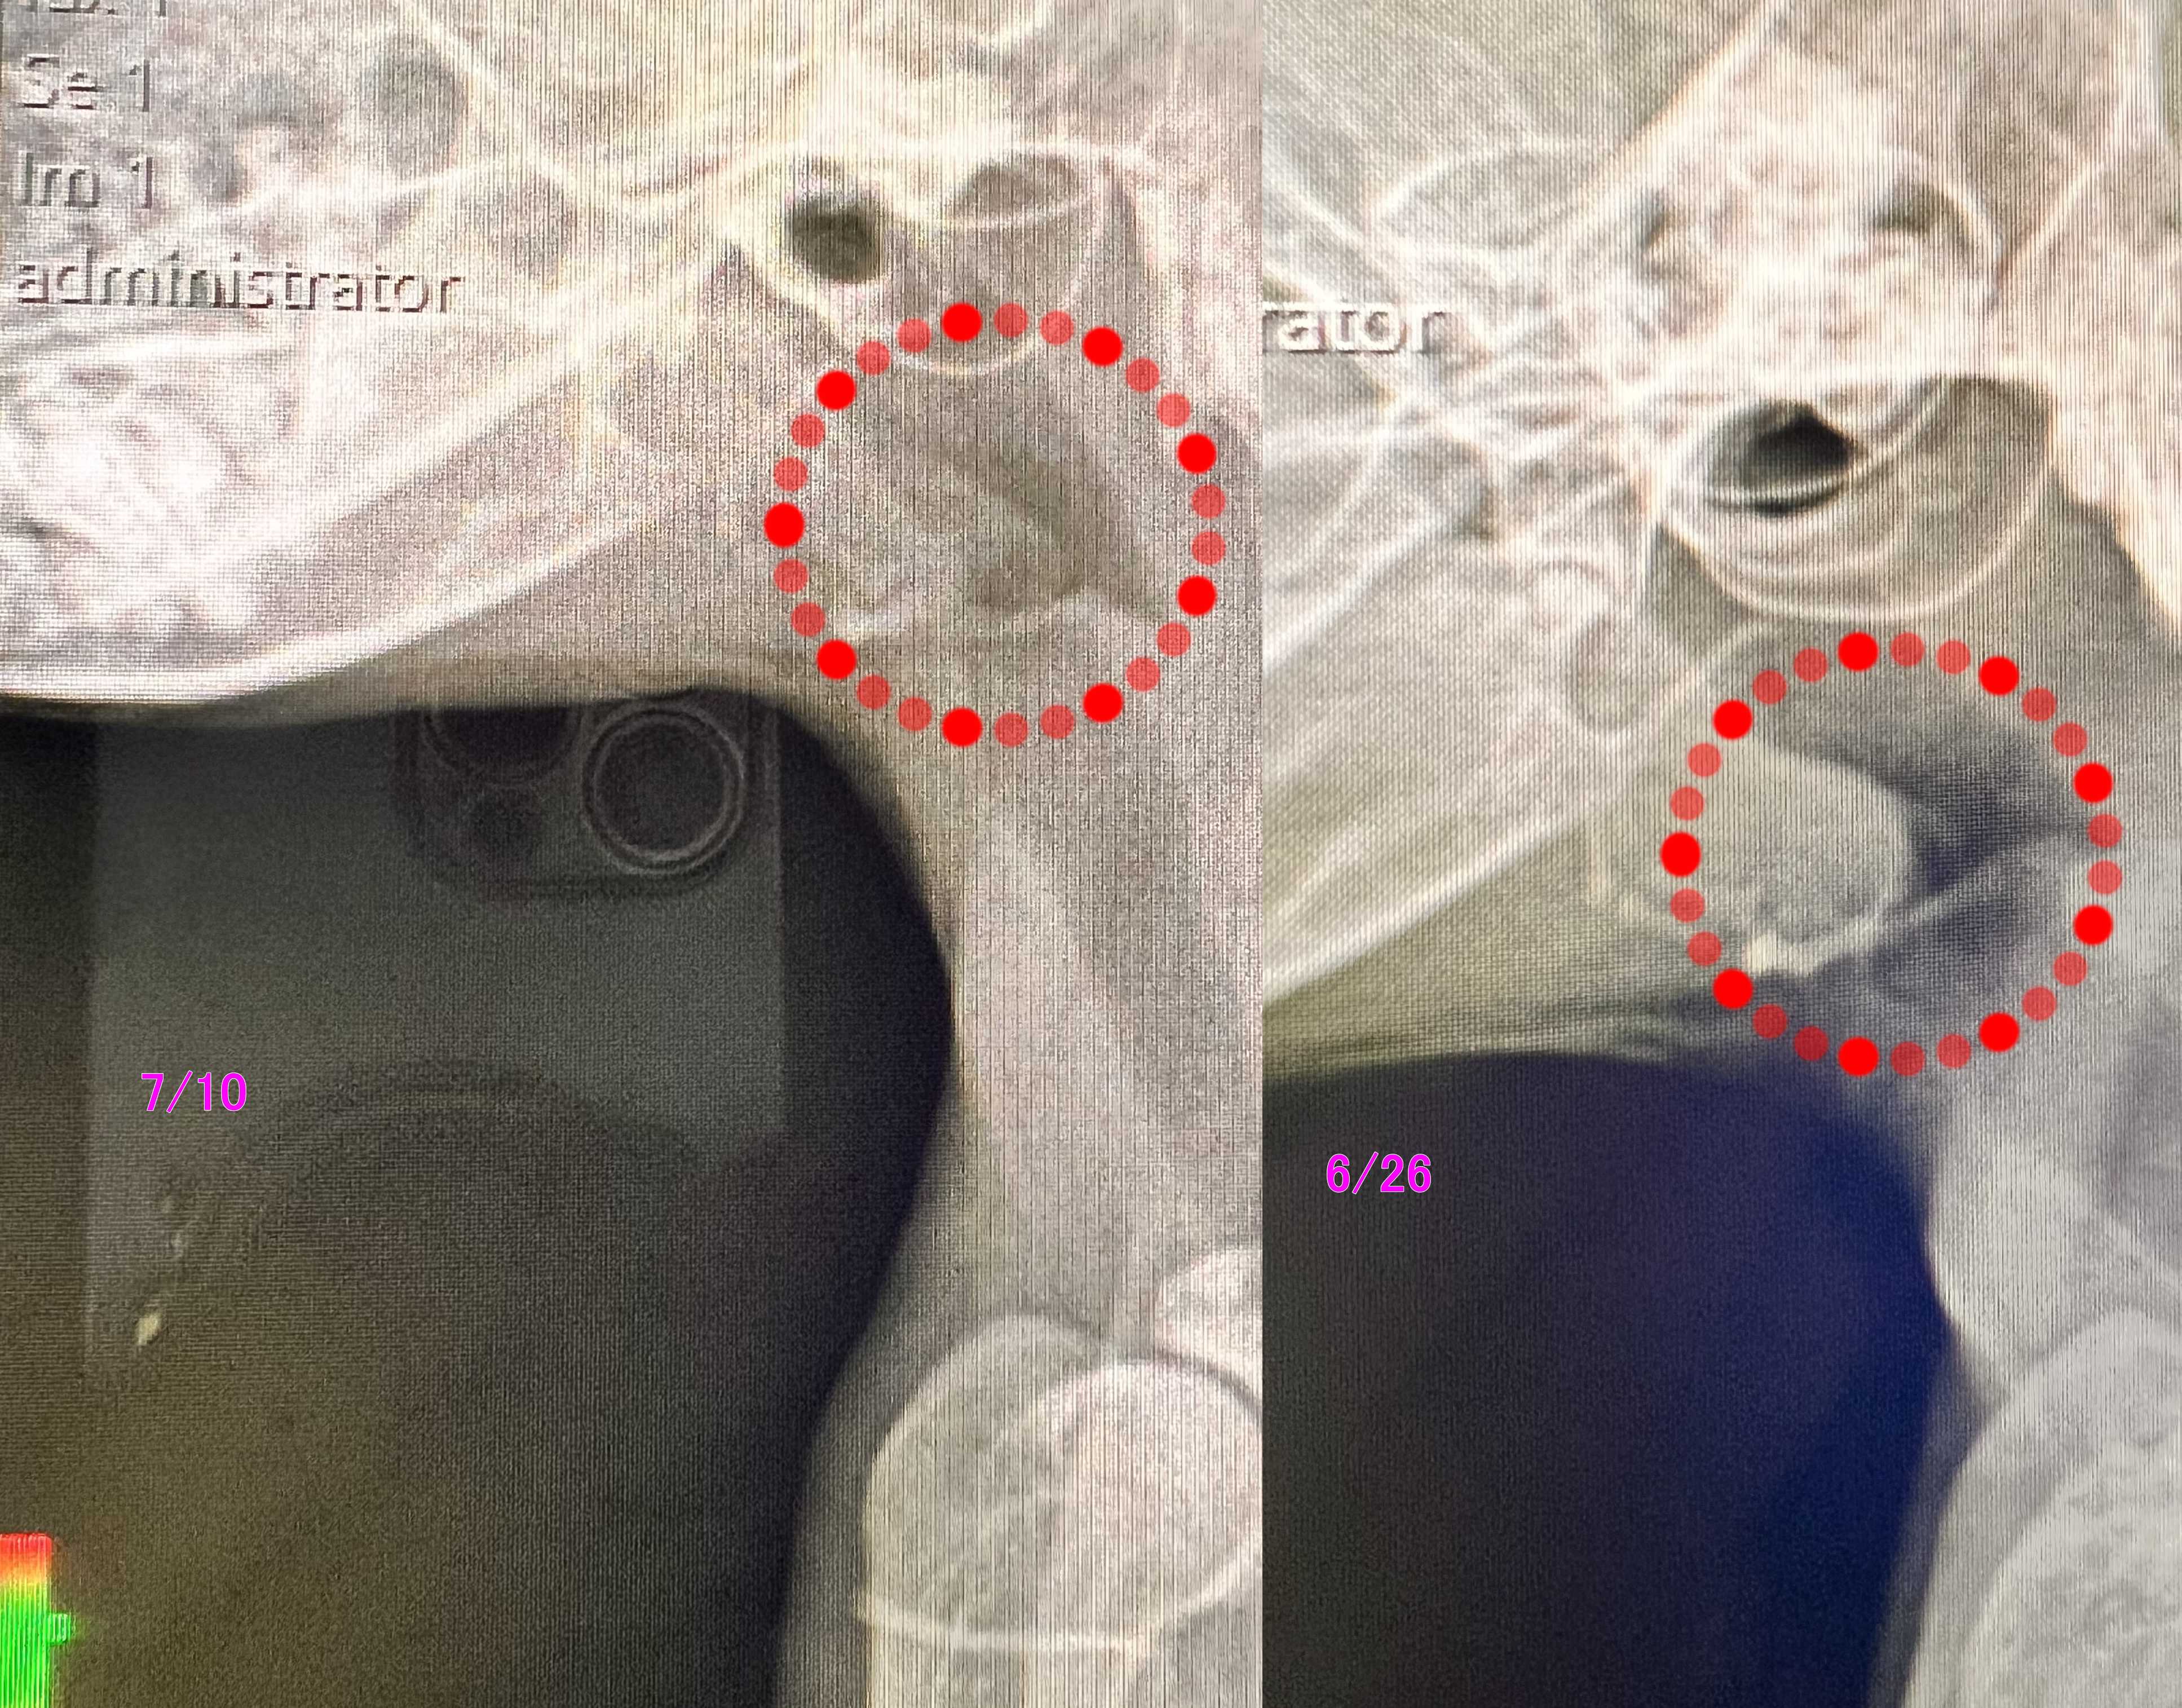

きなこ姐さん レントゲンは

喉元の扁平上皮癌か肉芽腫か?の疑い物は

消えてきているので

引き続き抗生剤を毎日

ステロイドは一日おきの半分量で

一か月後に再レントゲン確認。。。